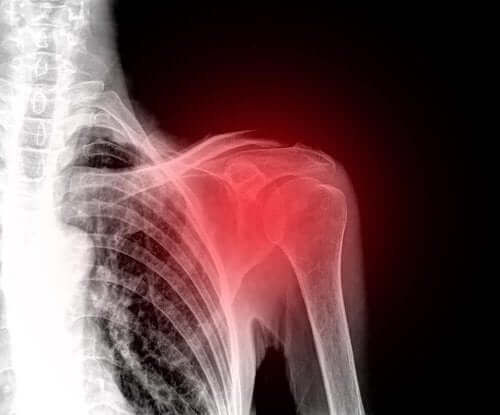

Kiertäjäkalvosimen repeämä on yleinen olkapäävamma keski-ikäisillä. Se onkin näin ollen yksi johtavista olkapääkivun syistä. Tässä artikkelissa kerromme kaiken, mitä kiertäjäkalvosimen repeämästä tulee tietää.

Oireet riippuvat vamman vakavuudesta. Pääasiallinen oire on kuitenkin olkapään kipu ja tämän nivelen kaikkien liikkeiden rajoittuminen.

Aluksi lääkäri tekee fyysisen tarkastuksen kiertäjäkalvosimen repeämän diagnosoimiseksi tutkimalla olkapään liikkuvuutta, vahvuutta ja mahdollista nivelkipua.

Lääkäri hyödyntää usein myös täydentäviä kokeita kuten ultraääni- tai magneettikuvausta, sillä ultraäänikuvauksella jänteitä ja lihaksia on mahdollista tutkia ihmisen liikkuessa. Tämän lisäksi se on edullinen ja ei-invasiivinen menetelmä.